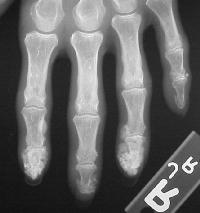

Xrays show extensive soft tissue calcifications of the distal pulp of these fingers.

Soft tissue calcifications are typically diffuse, and can not be simply "shelled out". Thorough excision may lead to extensive skin loss, and partial removal (limited incision and drainage) may be a reasonable compromise approach in selected cases.